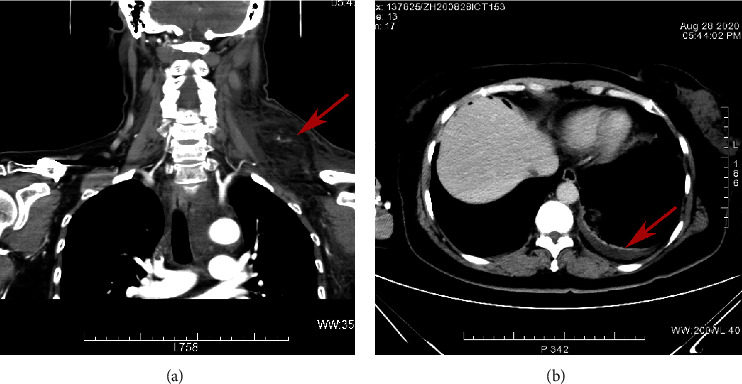

Abstract Image